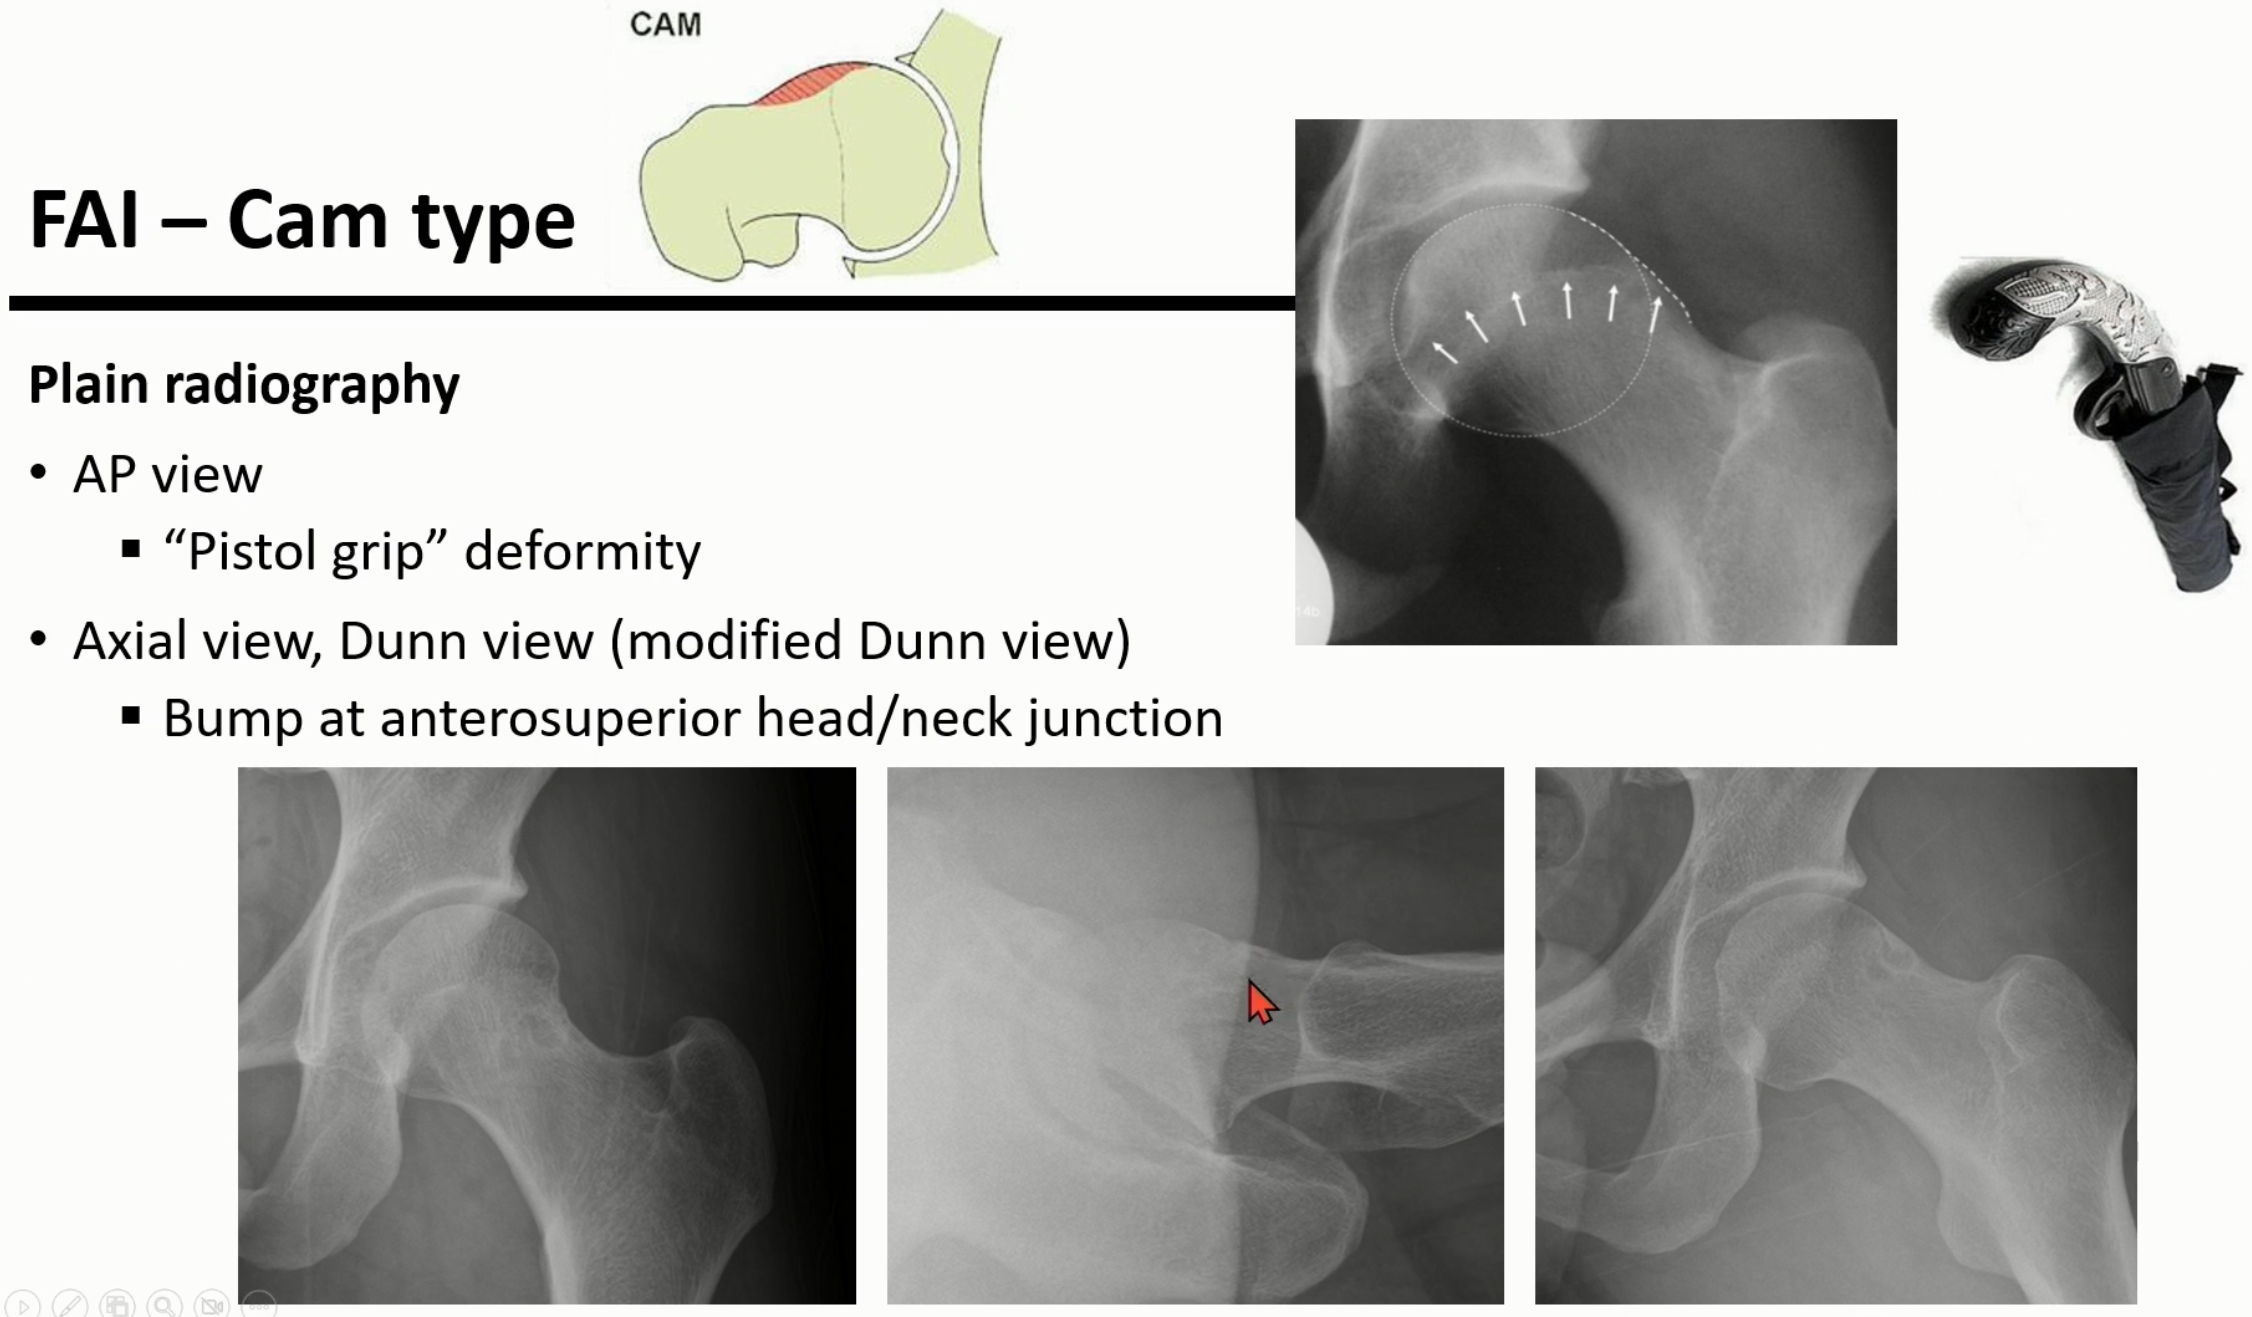

2. CAM type FAI ( 대퇴골의 모양이 이상한 경우)

CAM type은 대퇴골이 우측 위의 권총의 모양처럼 휘어지면서 굽은 형태를 보이는 경우를 말합니다.

그래서 흔히 pistol grip 모양이라고 부르기도 합니다.

CAM은 동력 장치에서 배웠던 CAM에서 기인한 것입니다.

Axial 또는 modified dunn view에서 femur의 head와 neck의 사이에서 bump로 관찰됩니다.

(빨간 화살표)

CT나 MRI에서는 더 확실하게 볼 수 있습니다.

head/neck junction 부위에 cyst나 bump가 보이며, head의 구형이 소실된 모습을 볼 수 있습니다.